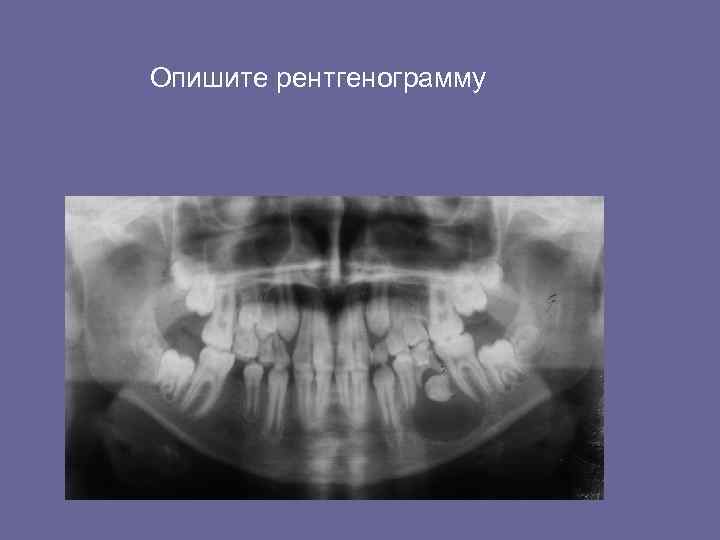

Взаимоотношение кист с зачатками постоянных зубов. Опишите рентгенограмму.